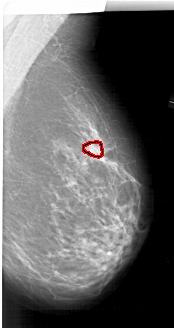

A_1330_1.RIGHT_CC

RIGHT_CC LINES 6526 PIXELS_PER_LINE 3376 BITS_PER_PIXEL 12 RESOLUTION 43.5 OVERLAY

FILE: A_1330_1.RIGHT_CC.OVERLAY

TOTAL_ABNORMALITIES 1

ABNORMALITY 1

LESION_TYPE CALCIFICATION TYPE PLEOMORPHIC DISTRIBUTION LINEAR

ASSESSMENT 4

SUBTLETY 2

PATHOLOGY BENIGN

TOTAL_OUTLINES 1

BOUNDARY